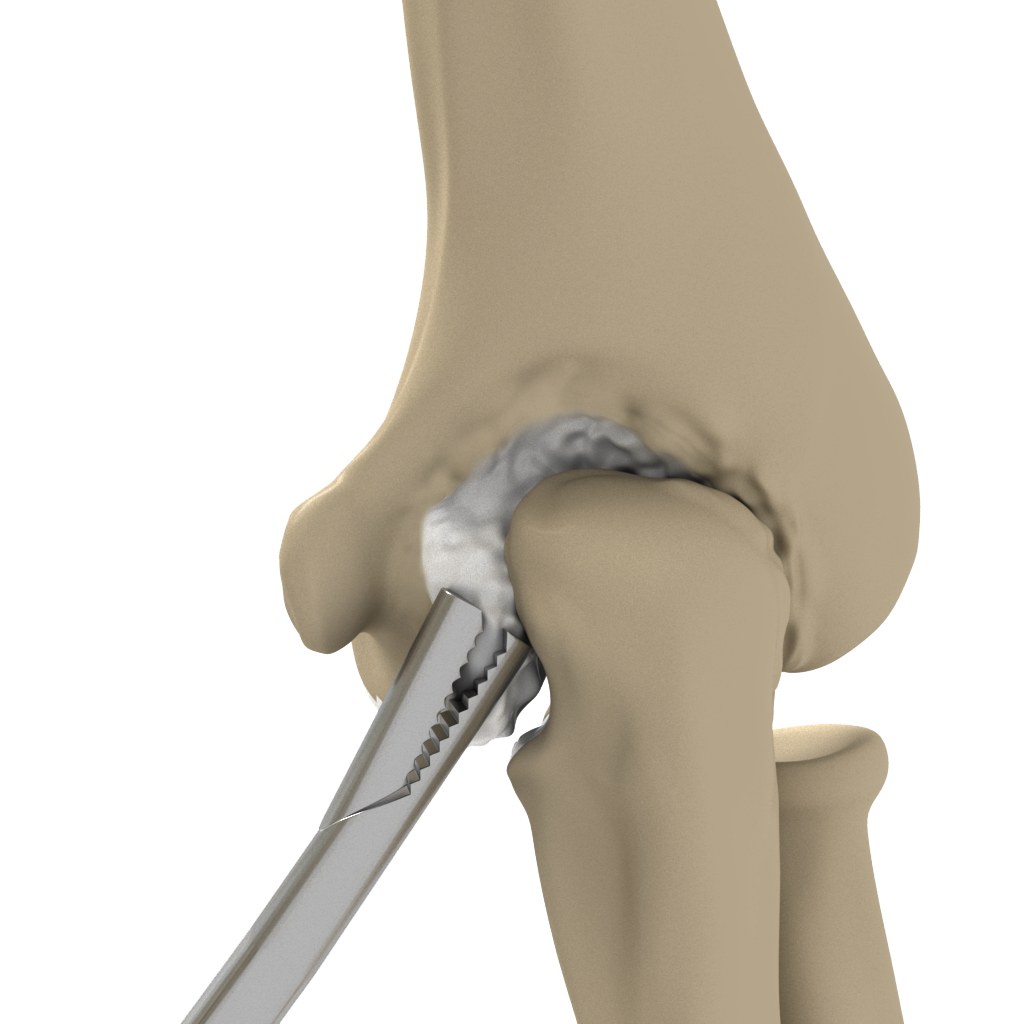

Elbow Arthroscopy

Elbow arthroscopy, also referred to as keyhole or minimally invasive surgery, is a surgical procedure performed through tiny incisions

Open Elbow Surgery

Open elbow surgery is an operative procedure performed to treat certain conditions of your elbow through a large, open cut (incision) in the skin using a scalpel.